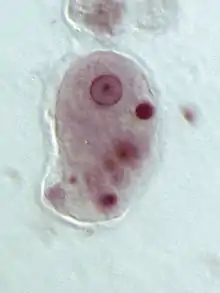

Le genre Entamoeba se caractérise par un noyau ayant l'aspect d'un anneau après coloration, avec une chromatine disposée en petit amas central (dit caryosome) et en couche périphérique.

Entamoeba histolytica peut se présenter sous deux aspects différents : le trophozoïte, forme cellulaire végétative mobile et de multiplication, et le kyste, forme immobile, de résistance et de contamination[11].

Le trophozoïte présente à son tour deux formes :

- Entamoeba histolytica minuta, de petite taille (en latin : minuta signifie « petit »), soit 10 à 15 µm. C'est une forme infestante qui se comporte en saprophyte restant à l'intérieur du colon, et qui ne donne aucun symptôme (sujet «porteur sain»).

- Entamoeba histolytica histolytica, plus volumineuse, de 20 à 30 ou jusqu'à 40 µm. C'est une forme invasive, véritablement parasitaire, hématophage, qui envahit la muqueuse colique et peut migrer vers d'autres organes, en étant responsable de l'amœbose maladie.

Entamoeba histolytica histolytica présente le même aspect général que minuta, avec des caractères supplémentaires, comme la présence d'hématies en voie de digestion dans des vacuoles cytoplasmiques (d’où le nom d’histolytica)[11].

Le kyste (10 à 16 μm) est sphérique, entouré d'une enveloppe résistante. Initialement, un kyste immature contient une vacuole stockant du glycogène, des agrégats de ribosomes, et un noyau. Par division du noyau, le kyste mûrit en deux puis quatre noyaux pour devenir un kyste à pouvoir infectieux[16]. Il survit au minimum 10 jours à 18 °C, ou 3 mois à 4 °C, dans le milieu extérieur[17]. C'est la forme de dissémination, qui résiste bien aux agents chimiques.